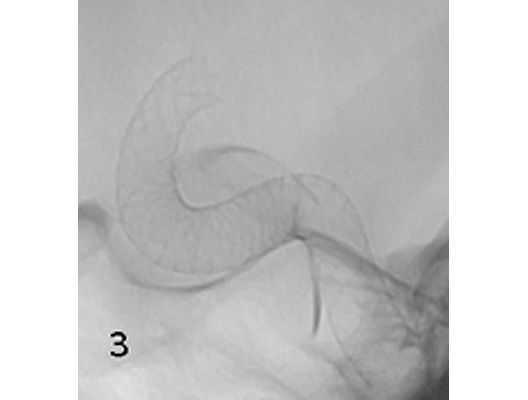

Angiographie: Behandlung von Aneurysmen

Behandlung von Aneurysmen

Aneurysmen an der Gefäßen des Gehirns können in vielen Fällen minimalinvasiv durch einen Zugang durch das Gefäßsystem, zumeist von der Leiste aus behandelt werden (sog. Endovaskuläre Therapie). Dabei gibt es z.B. die Möglichkeit ein Aneurysma durch Einbringung von Platinspiralen zu verschließen (sog. Coiling). Auch für komplexe Aneurysmen stehen inzwischen verschiedene endovaskuläre Methoden zur Verfügung.

Das Beispiel zeigt die angiographischen Bilder einer Patientin, bei der es zu einer Sehstörung gekommen war. Die Ursache war ein großes Aneurysma der Halsschlagader an der Schädelbasis (Bild 1). Bild 2 zeigt die Lage des Aneurysmas hinter dem Auge. Durch den Druck des Aneurysmas auf den Sehnerv war es zu der Sehstörung gekommen. Die Patientin wurde mit einer speziellen Gefäßprothese versorgt, welche über eine Punktion der Leistenarterie in die Halsschlagader eingesetzt wurde (Bild 3). Bei der Kontrolle nach 6 Monaten zeigte sich ein vollständiger Verschluss des Aneurysmas (Bild 4). Die Sehstörung hatte sich vollständig zurückgebildet.